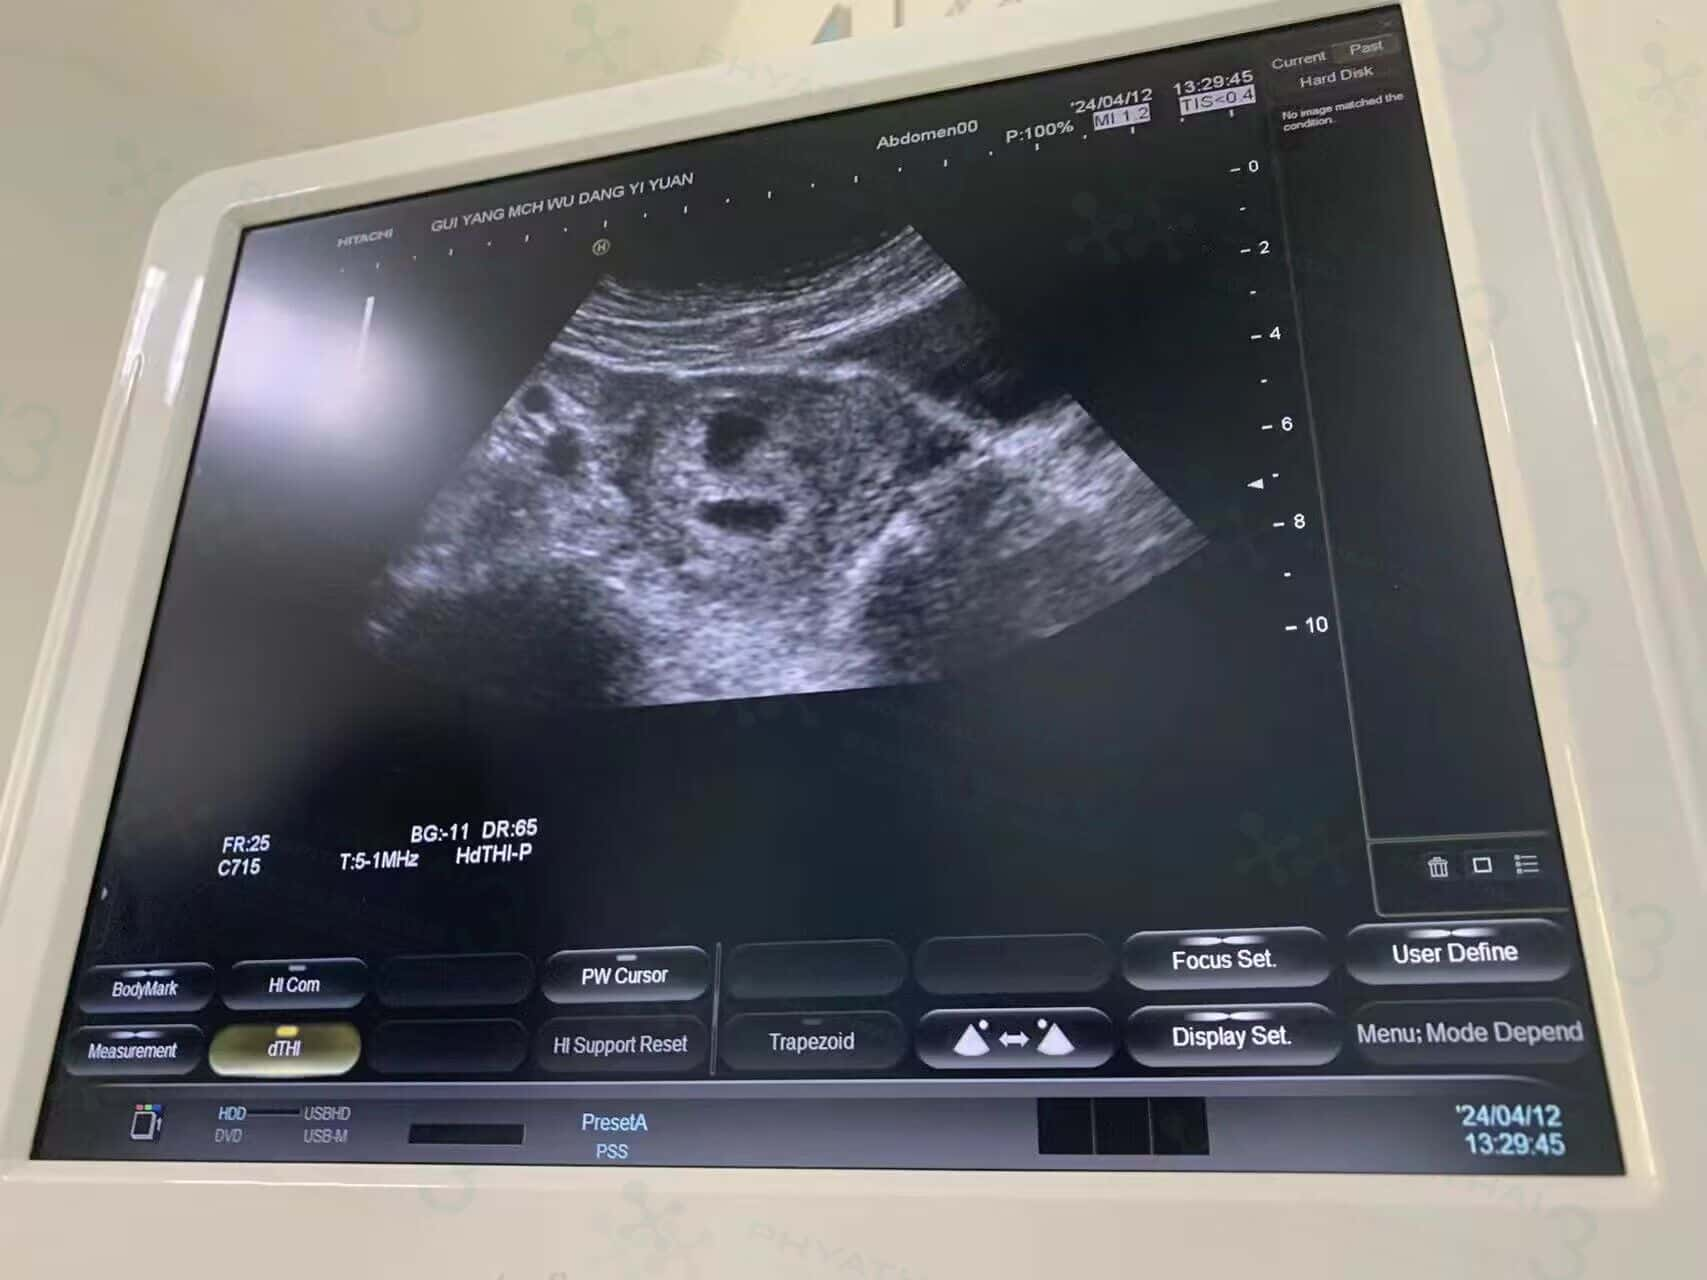

三队双胞胎看到胎心啦~

上个月好孕接龙宝宝回去的三个家庭 今天到了孕期六周 按照医生给写的流程去做检查,大家发报告过来两个双胎小王子 一个双胎小公主 今天都有看到胎心了 真的替患者开心 成双成对 后面也顺顺利利到出生哦